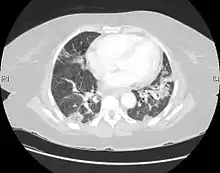

| CT scan of a patient with UIP. There is interstitial thickening, architectural distortion, honeycombing and bronchiectasis. | |

UIP may be diagnosed by a radiologist using computed tomography (CT) scan of the chest, or by a pathologist using tissue obtained by a lung biopsy.

Radiologically, the main feature required for a confident diagnosis of UIP is honeycomb change in the periphery and the lower portions (bases) of the lungs.[3]

On high-resolution computed tomography (HRCT), the following categories, depending on imaging findings, have been recommended by a collaborative effort by the American Thoracic Society, European Respiratory Society, Japanese Respiratory Society, and the Latin American Thoracic Society:[4]

- UIP pattern:[4]

- Honeycombing, with or without peripheral traction bronchiectasis; or bronchiolectasis (dilatation of the terminal bronchioles)[5]

- Predominantly subpleural and basal

- Often heterogenous distribution, being occasionally diffuse, and may be asymmetrical

There may be superimposed CT features such as mild ground-glass opacity, reticular pattern and pulmonary ossification.

- Probable UIP pattern:[4]

- Often heterogenous distribution

- Reticular pattern with peripheral traction bronchiectasis or bronchiolectasis

- There may be mild ground-glass opacity